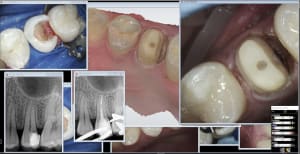

limites sous gingivales.JPG